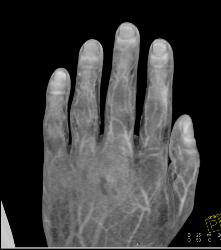

Cellulitis With Normal Vascular Arcade- in Multiple Displays